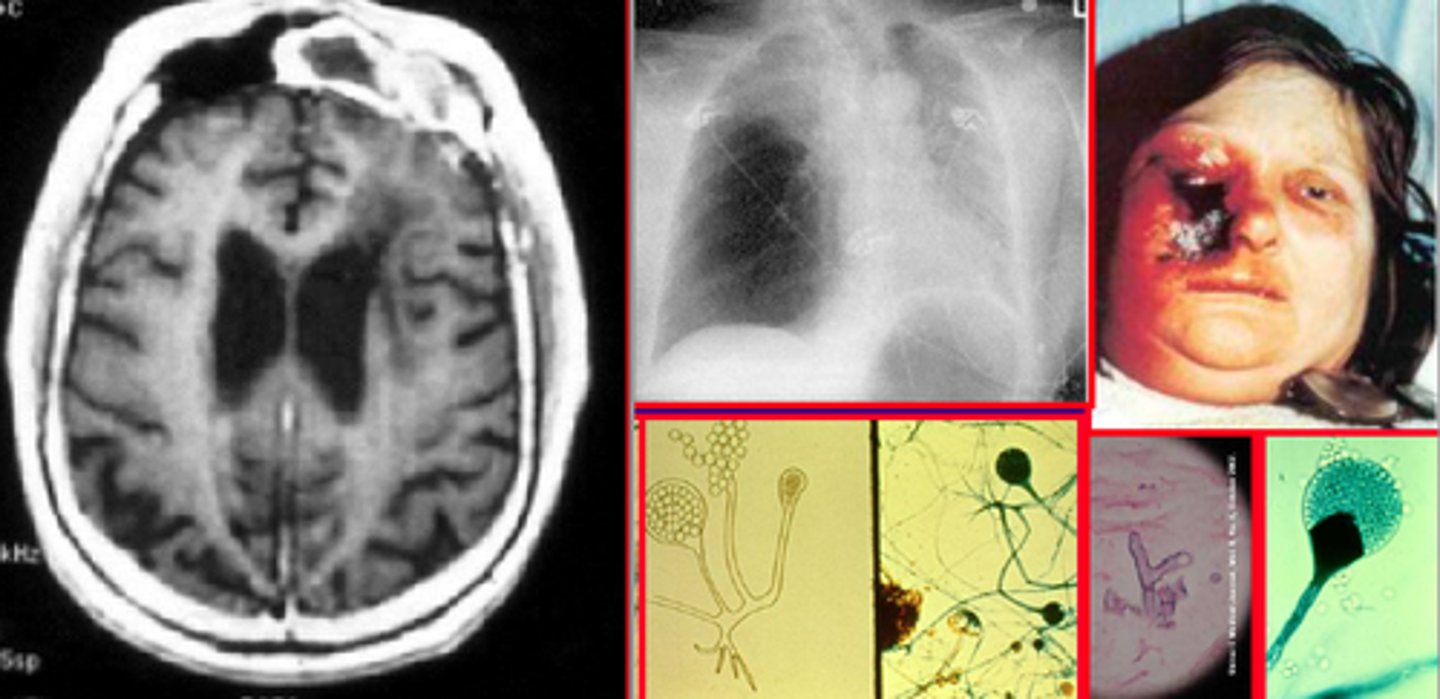

Black eschar on face of patient with diabetic ketoacidosis

Mucor or Rhizopus fungal infection

Travels through cribiform plate vessels